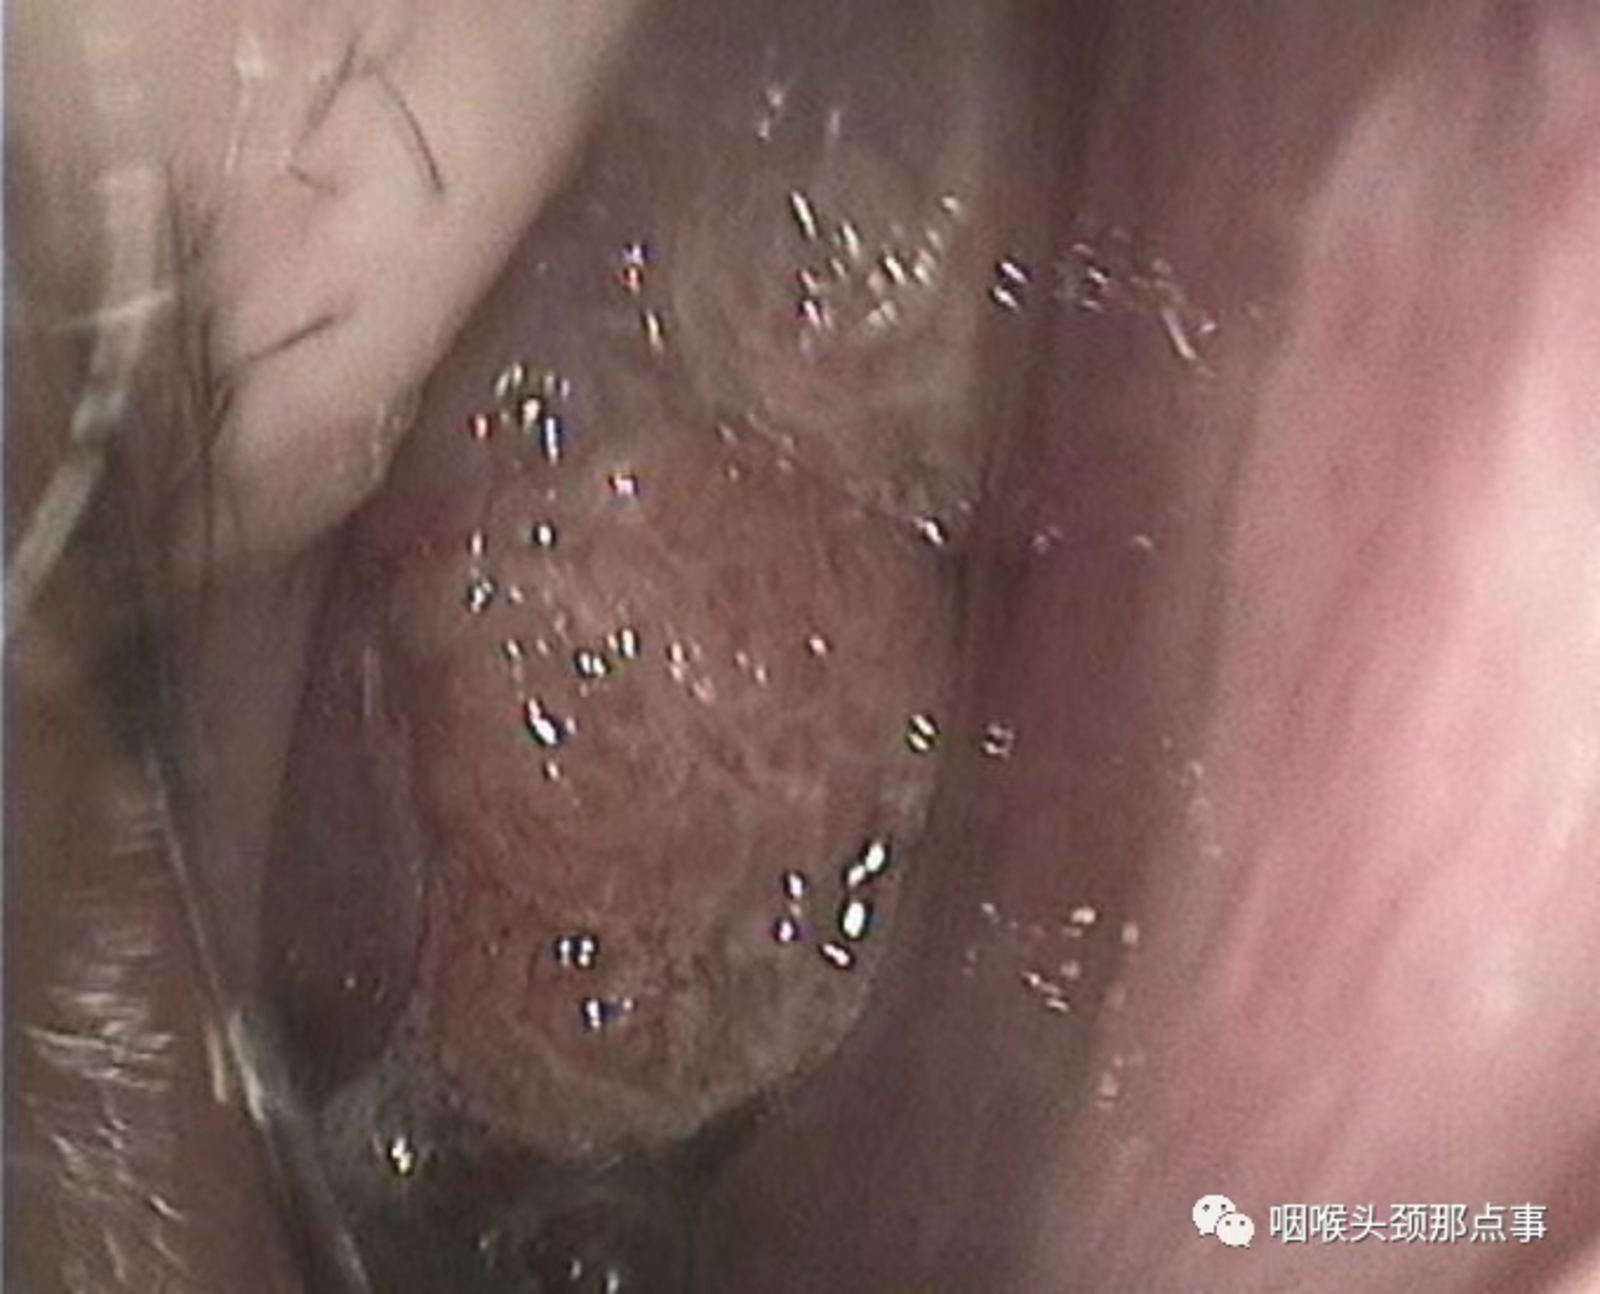

现在随着工业发展及大气污染,过敏性鼻炎患者患病率也明显增高,过敏性鼻炎常表现为鼻甲肿大,苍白水肿,患者鼻塞较明显,鼻音很重,夜间打呼憋气;肥厚性鼻炎也是重要原因之一;再有就是良性的比如鼻息肉、鼻腔乳头状瘤、骨化性纤维瘤等鼻腔堵塞;还有就是鼻腔恶性肿瘤等堵塞整个鼻腔导致的张口呼吸。

鼻乳头状瘤

鼻息肉